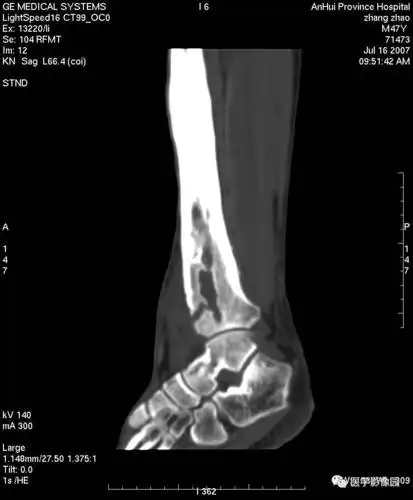

第八章骨骼与软组织第四节骨感染一化脓性骨髓炎丨精品连载